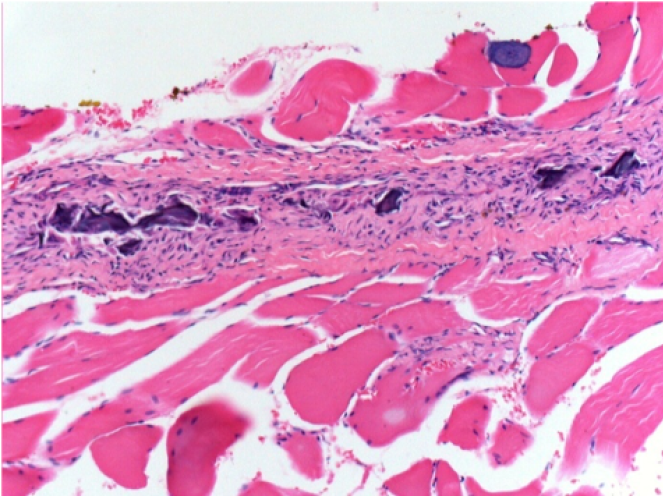

1 mese dopo Iniezione Endopeel

Scatola Nr 3

1 mese dopo Iniezione 0.1ml di Endopeel nel muscolo pretibiale destro ( Dx) .

Che cosa viene visualizzato in nero nella figura Sx : 100x-Giorno30 non é una necrosi come potrebbe immaginare un dilettante.

In effetti, 4 conclusioni devono essere prese in considerazione

- un artefatto di colorazione

- un`assenza di necrosi

- un`apoptosi

- un processo biorigenerativo

Sx : Controllo-100x-Giorno30

Dx:100x-Giorno30

Dx :400x-Giorno30